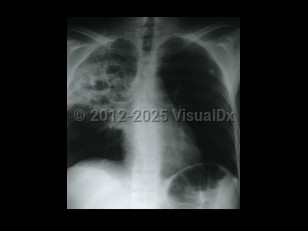

Chest pain, Pleural effusion, 50-59 year old Female

TuberculosisTuberculosis